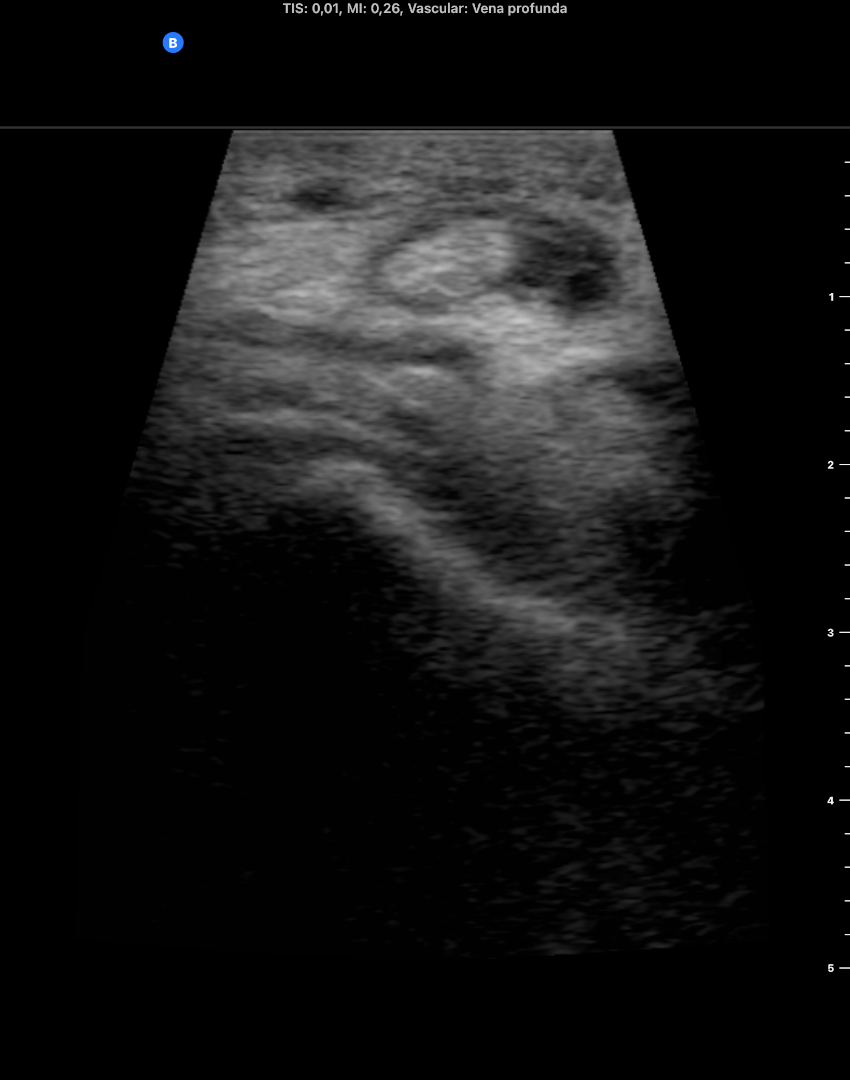

Descripción de los hallazgos ecográficos y las imágenes más relevantes para la resolución del caso

EcoscopiAP: líquido peritendinoso alrededor del tendón del m tibial anterior. Mínimo edema del tj cel sc. No TVP.